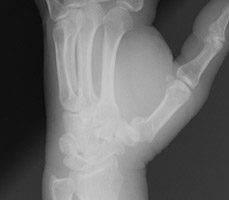

- Click on the image for a larger versionCPA radiograph of the hand. This shows fractures of both the third and fourth metacarpals as well as a Colles fracture.